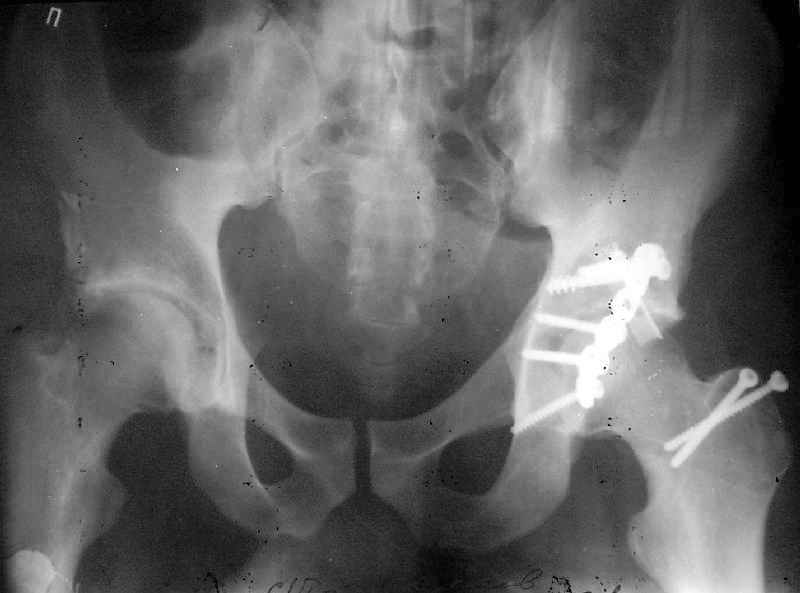

Пациент переведен в нашу клинику на 5 день после множественной травмы 25.01.2003 - двустороннее повреждение вертлужных впадин, разрыв левого крестцово-подвздошного сочленения. Вывихи обоих бедер. В месте первичного поступления подвздошный вывих правого бедра вправлен 26.01.2003, наложено вытяжение за левую вертельную область. Остеосинтез левой вертлужной впадины выполнен у нас 6.02.2003. Вопрос: надо ли синтезировать задне-верхний край правой вертлужной впадины?

Оперировать задне-верхний край необходимо. Развитие в последующем коксартроза почти стопроцентно. Отсутствие заднего края серьёзно осложнит протезирование.

правую впадину собрали здорово! Мои поздравления Рункову. Сами меня учили-учили, а где же запирательная проекция левой вертлужной

впадины. Такое впечатление что на КТ есть интерпозиция кусочком, тогда уж точно надо туда залесть, а так, я считаю не стоит.

Уважаемый Алексей, через месяц после повреждения обострять травму, чтобы продлить "колясочный" срок? Второй сустав станет опорным не скоро.Головка на Ртг концентрически вставлена, задний фрагмент не интерпонирует, лимбус,по видимому тоже, ямочный фрагмент мешать не должен,герметизирующую манжету адекватно восстановить, обычно, не удается. Выгоды от оперативного вмешательства сомнительны. Я бы оперировать не стал.Еще месяц без нагрузки (по меньшей мере) и в нашей "конторе"- МОНИКИ(Вы наверняка знаете О.Ш.Буачидзе) положились бы на ощущения пациента при активных движениях правым бедром. Можно и сейчас проверить на возможность блокады и тогда принимать окончательное решение.

Поздравляю с отлично выполненой репозицией при остеосинтезе !

Согласен, что нужна вторая проекция.

Если нагрузка на конечности будет не ранее 5-6 недель,оперировать не стоит. Считаю, что эндопротезирование справа не будет нужным.